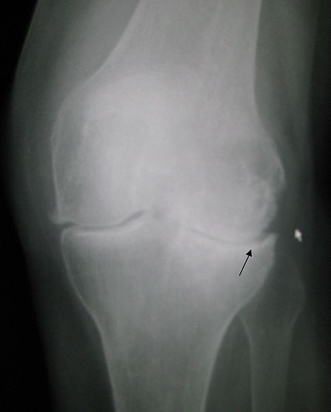

- Imaging (X-ray):

- Joint space narrowing

- Subchondral sclerosis

- Osteophyte formation (“joint lipping”)

- Varus deformity

- Possible ankylosis in late-stage disease